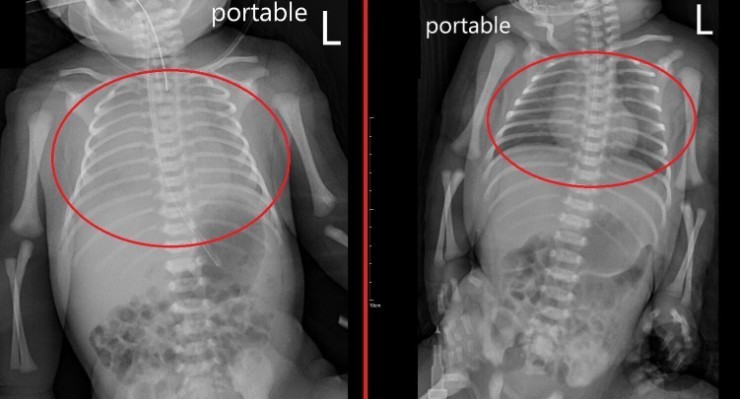

Qua thăm khám và làm các xét nghiệm cần thiết, các bác sĩ chẩn đoán bé mắc viêm phổi bẩm sinh – một trong những bệnh nhiễm trùng nguy hiểm ở trẻ sơ sinh. Theo bác sĩ Tôn Nhược Nghiêu, Trưởng khoa Nhi, bệnh có thể làm suy giảm nghiêm trọng chức năng trao đổi khí của phổi. Nếu không được can thiệp kịp thời, nguy cơ tử vong là rất cao.

Do tình trạng suy hô hấp nặng, ê-kíp điều trị đã tiến hành đặt nội khí quản, sử dụng máy thở để duy trì oxy cho cơ thể, đồng thời kết hợp điều trị bằng kháng sinh nhằm kiểm soát nhiễm trùng. Sau nhiều ngày được theo dõi sát sao, tình trạng của bé dần ổn định. Đến ngày thứ 6, trẻ được cai máy thở thành công và xuất viện sau 10 ngày điều trị trong tình trạng khỏe mạnh.